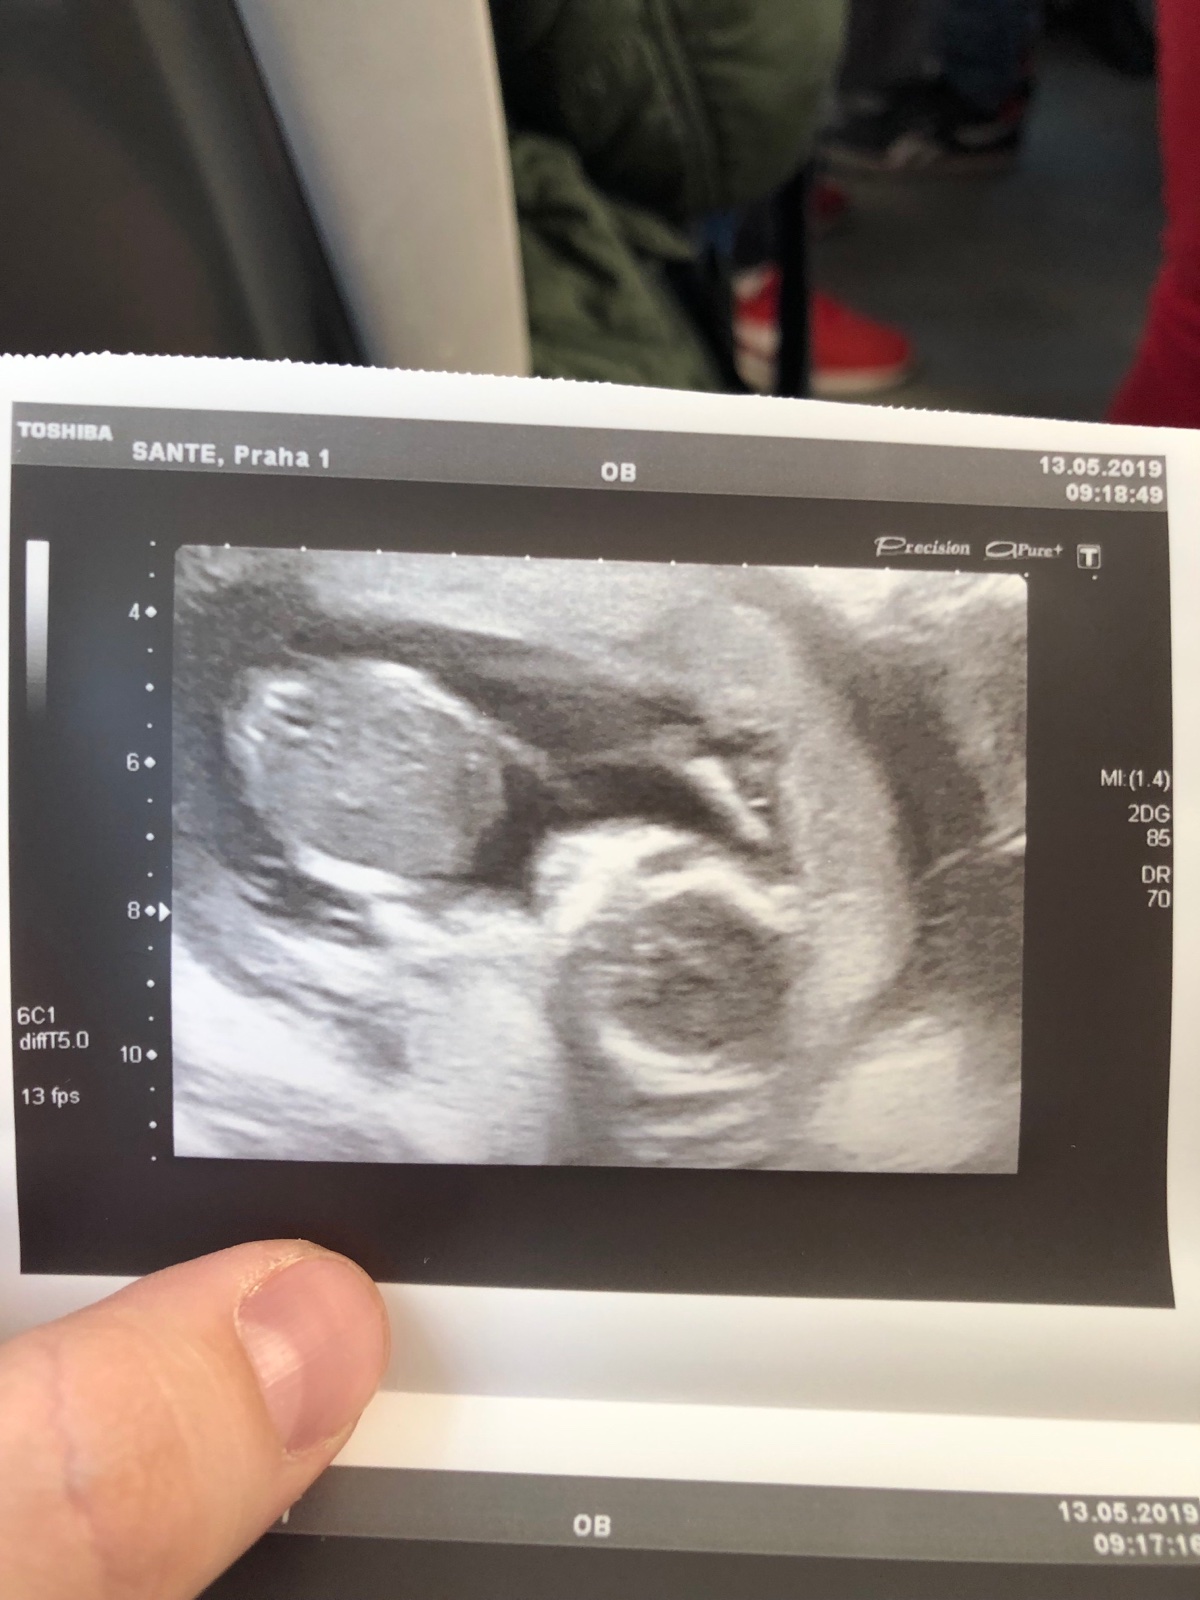

@makronka222 Ruce dokážu lokalizovat, ty mi doktorka na fotce ukázala 🙂. Nohy jsem neviděla, doufám, že je má :D. Já osobně vidím jen rozmazané fleky, ale třeba tu má někdo zkušené oko 🤷♀️.

Z tyhle nekvalitni fotky asi tezko neco vyhledas. Muze tam dole byt ruka, snura, nohy krizem...